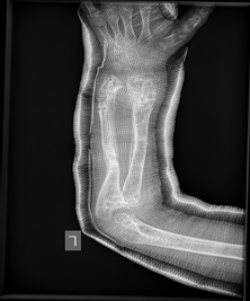

Olier’s disease

The images show a case of Olier’s disease which had a short and deformed forearm. He underwent surgical intervention by Dr. Zenios with the use of external osteosynthesis.

External osteosynthesis

Post-operative